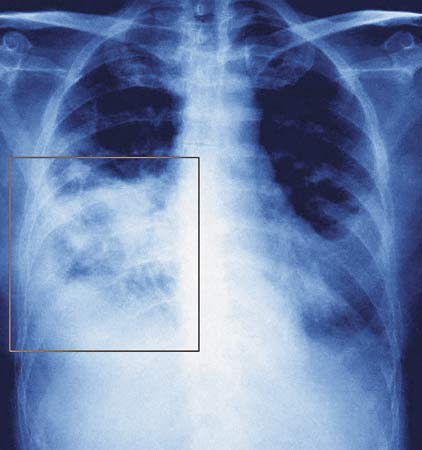

Лечение пневмоний  должно быть комплексным и состоит из этиотропного, патогенетического и симптоматического направлений лечения. Этиотропное, заключается в уничтожении микроорганизмов. По своему антибактериальному действию ВСЕ лекарственные травы и прочие народные средства НА МНОГО уступают синтетическим препаратам. Поэтому для этой цели должны использоваться только они (народные методы, как небольшое дополнение к ним), которые должны быть назначены только врачом (терапевт, инфекционист, пульмонолог), на основании клинической, рентгенологической, лабораторной картины заболевания.

Обязательным в лечении больных пневмонией является назначение антибиотиков. Однако перед назначением препаратов необходимо произвести посев мокроты на определение конкретного вида возбудителя. Но этот анализ будет готов не сразу, а лечение нужно назначать незамедлительно. Для этого прибегают к назначению антибиотиков широкого спектра действия, которые воздействуют на любую микробную флору. Лечение должно проводиться под лабораторным контролем, потому что микробы очень быстро становятся нечувствительными к определенному виду препарата. И если такое происходит, антибиотик следует сменить. Антибактериальные препараты должны применяться в таких дозах и с такими промежутками времени, чтобы в крови и в легочной ткани поддерживалась доза средства, оказывающая лечебный эффект. Доза и число антибактериальных препаратов зависят от тяжести течения заболевания (этот критерий определяется клинически, по таким симптомам, как температура, интоксикация, одышка, кашель, наличие мокроты) и распространенности процесса, что определяется рентгенологически.

Контроль лечения обязательно проводится и рентгенографически с оговоренными сроками. После выздоровления желательно проведение санаторно-курортного лечения.